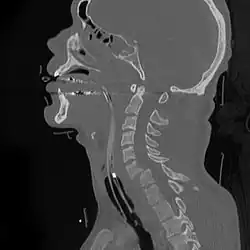

![]() | |

| A fracture of the base of the dens (a part of C2) as seen on CT | |

A cervical fracture, commonly called a broken neck, is a fracture of any of the seven cervical vertebrae in the neck. Examples of common causes in humans are traffic collisions and diving into shallow water. Abnormal movement of neck bones or pieces of bone can cause a spinal cord injury, resulting in loss of sensation, paralysis, or usually death soon thereafter (~1 min.), primarily via compromising neurological supply to the respiratory muscles and innervation to the heart.